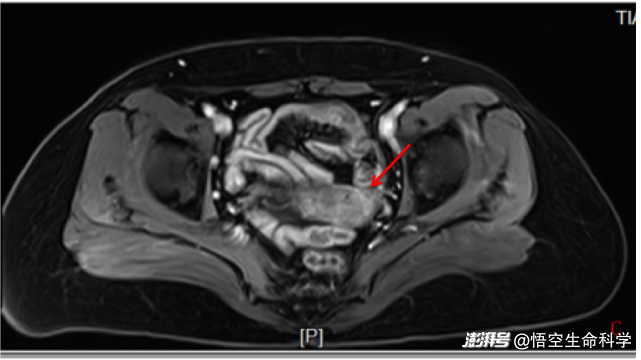

回輸后2個(gè)月,宮頸及腹腔未見明顯異常